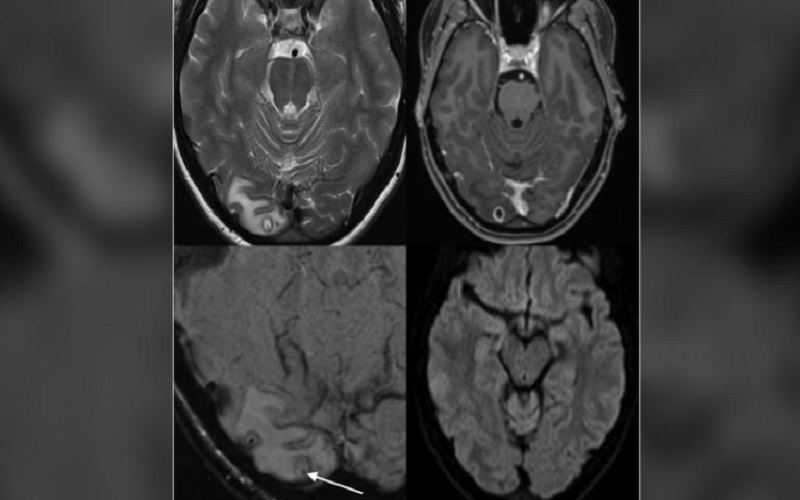

Hasil MRI yang menunjukkan kista berisi larva cacing pita di otak seorang perempuan Australia. (foto: CNN)

Berdasarkan penelitian yang diterbitkan dalam The American Journal of Tropical Medicine and Hygiene pada 21 September lalu, rasa sakit di bagian kepala yang dialami perempuan 25 tahun itu disebabkan oleh larva cacing pita yang berkembang biak di ruang otaknya.